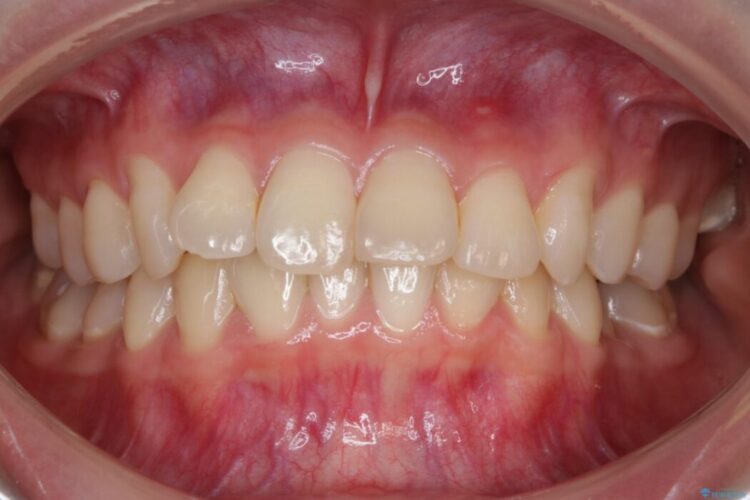

【20代女性】ブライダルに向けた矯正できれいなスマイルラインへ

笑った時に見える歯並びをきれいにしたいとの主訴で来院されました。

ガタつきの度合いから抜歯は不要と判断しましたので、マイクロインプラントを用いて歯全体を遠心移動させていくことでねじれや噛み合わせのズレを改善していく計画を立てました。